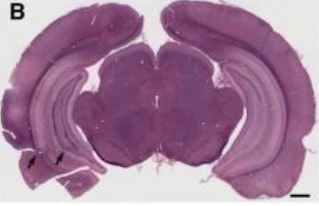

Possible involvement of lysosomal dysfunction in pathological changes of the brain in aged progranulin-deficient mice

-